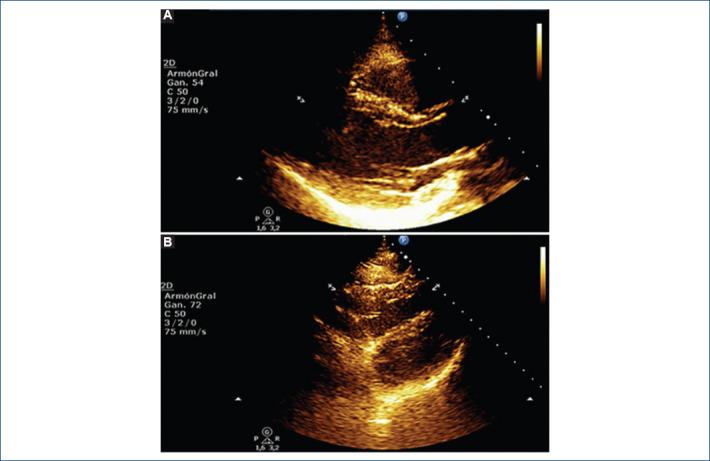

[SARS-COV-2 pericarditis: Case report].

Arch Cardiol Mex. 2021 Dec 20;91(Suplemento COVID):140-142. doi: 10.24875/ACM.21000033.

摘要